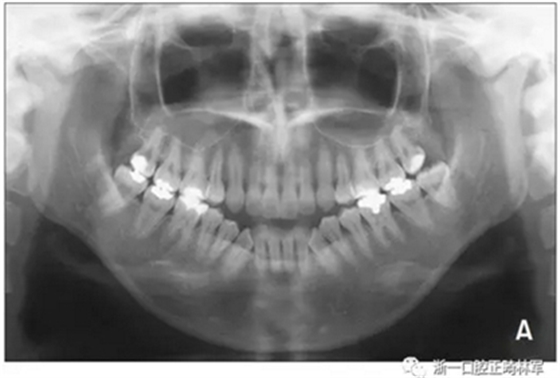

全景片顯示四顆智齒都存在,上頜切牙有牙根吸收,并且在雙側(cè)髁突都有相當(dāng)大的吸收(Figures 1B and 5A)。頭測分析顯示:ANB angle, 4.5°; FMA, 46.7°; U1-SN, 95.8°; L1-MP, 83.7°(Table 1, Figure 5B)。